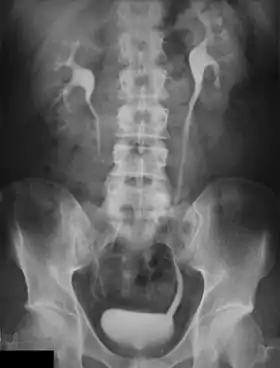

An Example of an IVU radiograph

An intravenous pyelogram (IVP), also called an intravenous urogram (IVU), is a radiological procedure used to visualize abnormalities of the urinary system, including the kidneys, ureters, and bladder. Unlike a kidneys, ureters, and bladder x-ray (KUB), which is a plain (that is, noncontrast) radiograph, an IVP uses contrast to highlight the urinary tract.

Immediately after the contrast is administered, it appears on an X-ray as a 'renal blush'. This is the contrast being filtered through the cortex. At an interval of 3 minutes, the renal blush is still evident (to a lesser extent) but the calyces and renal pelvis are now visible. At 9 to 13 minutes the contrast begins to empty into the ureters and travel to the bladder which has now begun to fill. To visualize the bladder correctly, a post micturition X-ray is taken, so that the bulk of the contrast (which can mask a pathology) is emptied.